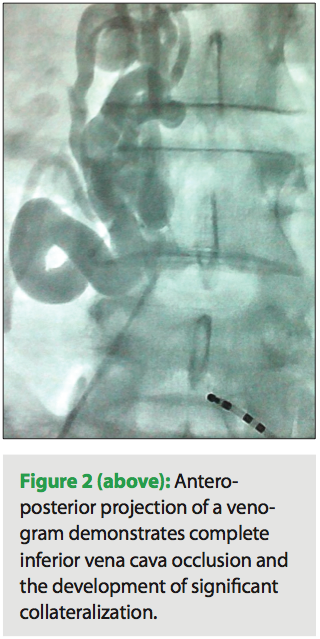

Venography of the left upper extremity was performed and demonstrated partial occlusion of the left subclavian vein with significant collateralization (Figure 1). Via a modified Seldinger technique, a guidewire was advanced into the subclavian vein. The RV lead implanted three months ago was removed with manual traction. Following sequential dilatations with additional sheaths, the new RV lead was advanced via the ipsilateral subclavian vein without complications. The decision was made to leave the previously abandoned five-year-old RV lead in place. Removal of that lead would have required laser lead extraction, and it was not immediately necessary to subject a frail, elderly woman to the potential risks of that procedure.